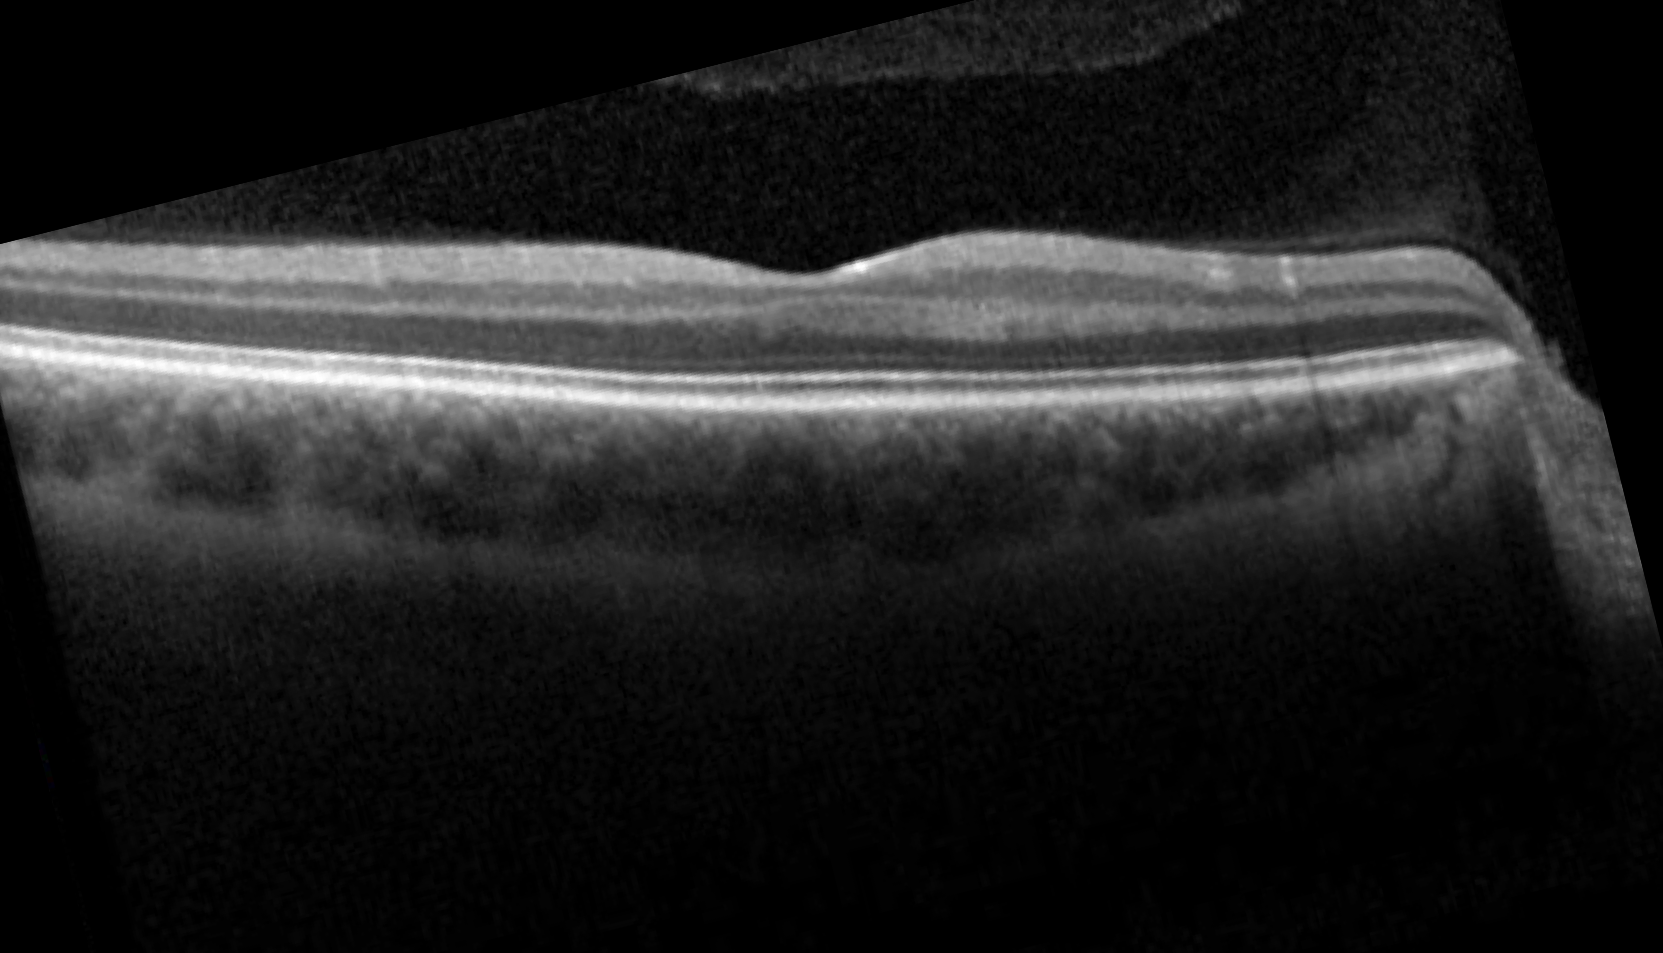

Optical coherence tomogram of the right eye.